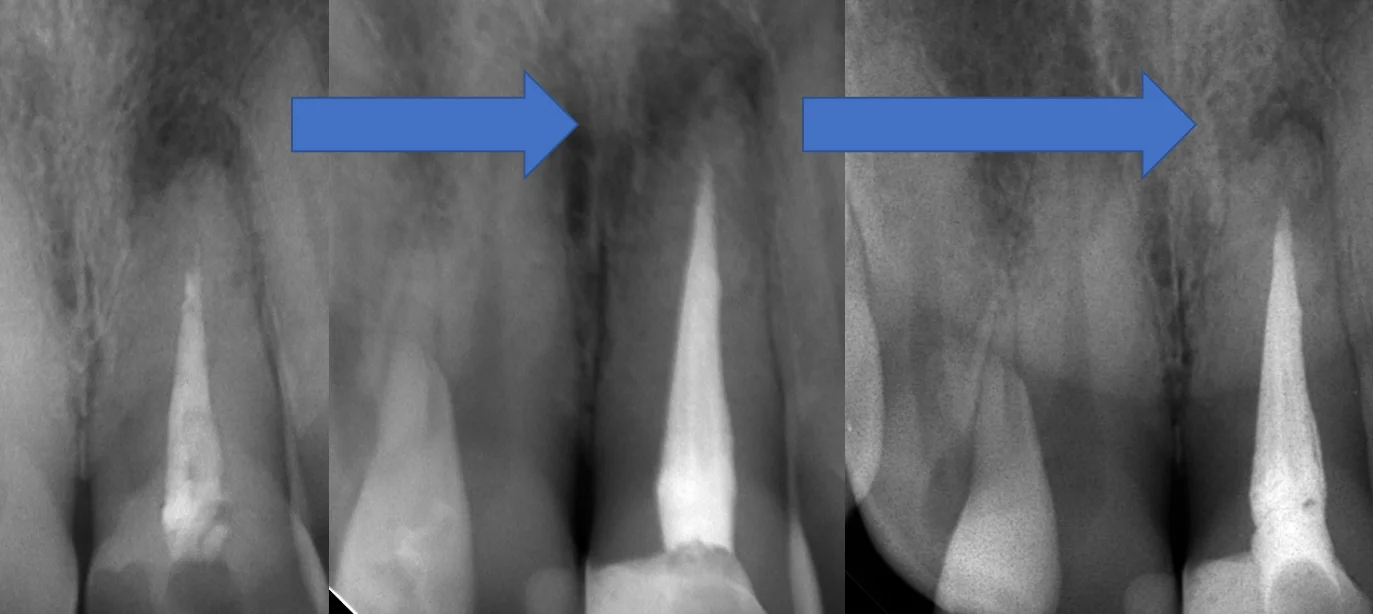

治療スタート時→根管充填時→根管充填から1年経過後のレントゲンがこちらです。

分かりやすくするために歯のサイズを大体揃えてみました。

根の先の膿が大分小さくなってきているのが分かるかと思います!